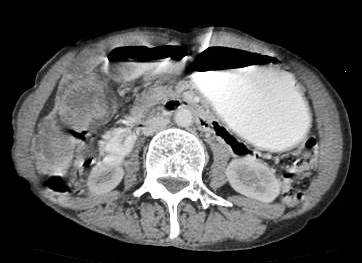

Common patterns of carcinoma gallbladder

Three patterns have been described on ultrasonography (US). The gallbladder fossa is replaced by a heterogeneous mass (figure 1) with internal areas of necrosis; or there may be diffuse, irregular, and asymmetrical wall thickening (Figure 2); or less commonly, a polypoidal, fungating intra-luminal mass is seen. Correct preoperative diagnosis has improved considerably with the use of newer imaging techniques [6-8]. Majority of cases when diagnosed, are no longer resectable (Figure 3) [9-11].

Figure 3: large polypoidal fungating gallbladder mass with gross invasion of liver parenchyma. Hepato-duodenal ligament invaded. Left lobe shows discrete secondaries.